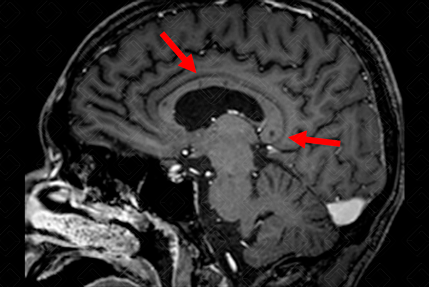

Texto alternativo para a imagem Figura 1. Créditos: Dra. Elazir Mota - Rio de Janeiro/RJ

Descrição da figura 1: Ressonância magnética do crânio T1 pós-contraste evidenciando lesões hipointensas no corpo caloso (lesões de aspecto perfurante) – setas vermelhas.

• Os principais achados são: Lesões em "bola de neve" no corpo caloso em T2/Flair, podendo evoluir para lesão perfurante em T1, microinfartos da cápsula interna ("colar de pérolas"), lesões de substância branca e realce meníngeo (figuras 1 e 2).